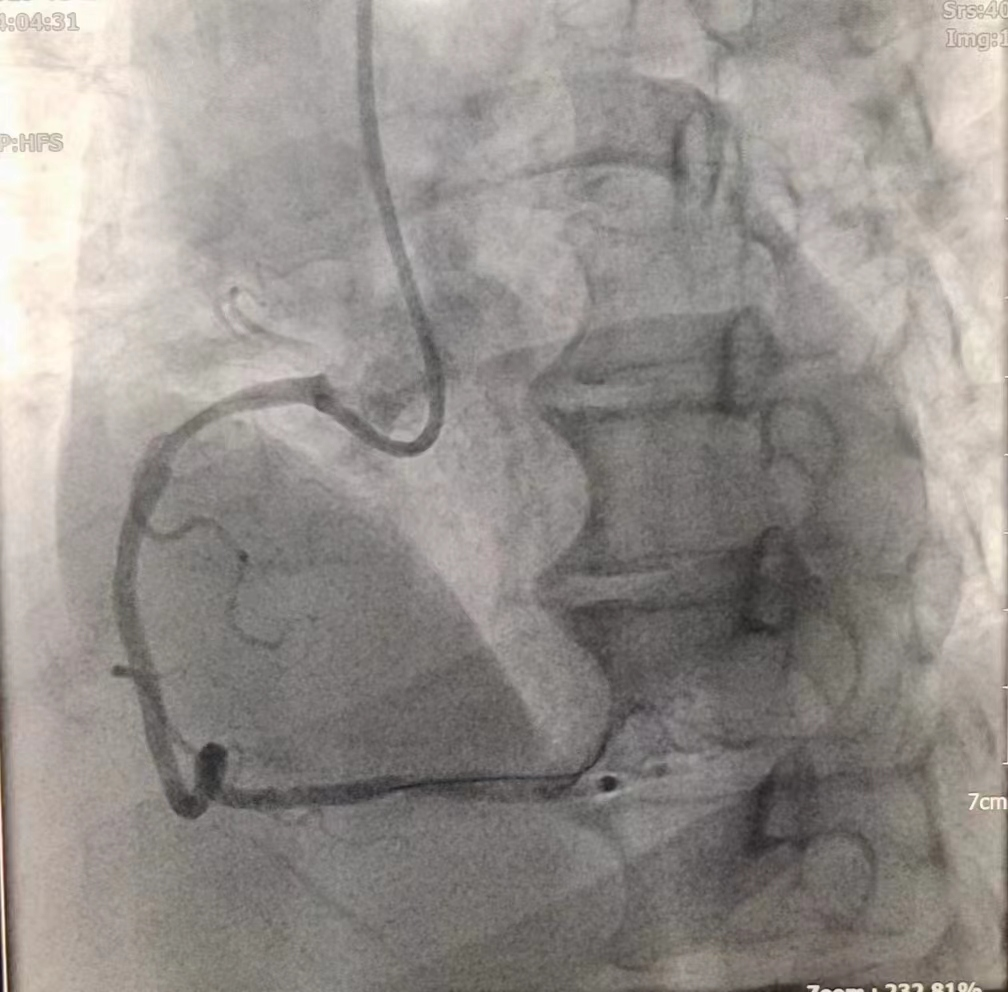

女性患者,49歲,突發(fā)暈厥急診我院,經(jīng)診斷為:冠狀動(dòng)脈粥樣硬化性心臟病、2型糖尿病。導(dǎo)入造影導(dǎo)管行冠狀動(dòng)脈造影示:冠狀動(dòng)脈分布呈左冠優(yōu)勢(shì)型,LM未見明顯狹窄,血流TIMI3級(jí);LAD全程多發(fā)斑塊,中段狹窄約60%,遠(yuǎn)端狹窄約50%,D1未見明顯狹窄,血流TIMI3級(jí);LCX未見明顯狹窄,血流TIMI3級(jí),RCA近端狹窄約50%,中段發(fā)出圓錐支后完全閉塞,血流TIMI0級(jí),急診開通血管并充分?jǐn)U張,殘余狹窄仍然嚴(yán)重。在與患者及家屬溝通時(shí),其了解得知臨床有一種新型的可吸收支架,植入體內(nèi)后支架能完全被降解和吸收,希望能用這種新型的支架進(jìn)行手術(shù)治療。由于生物可吸收支架有著嚴(yán)格的適應(yīng)癥,因此經(jīng)過嚴(yán)格篩選評(píng)估,最終對(duì)患者進(jìn)行了Xinsorb生物可吸收支架置入術(shù)。支架植入術(shù)前經(jīng)過充分預(yù)擴(kuò)張,按照規(guī)范的可吸收支架操作流程,快速送入可吸收支架到病變部位,精準(zhǔn)定位后14個(gè)大氣壓釋放,生物可吸收支架后擴(kuò)球囊擴(kuò)張。充分球囊后擴(kuò)張,以保證支架貼壁良好,血流速度正常,造影完美,手術(shù)順利結(jié)束。

(圖為生物可吸收支架置入術(shù)后影像)